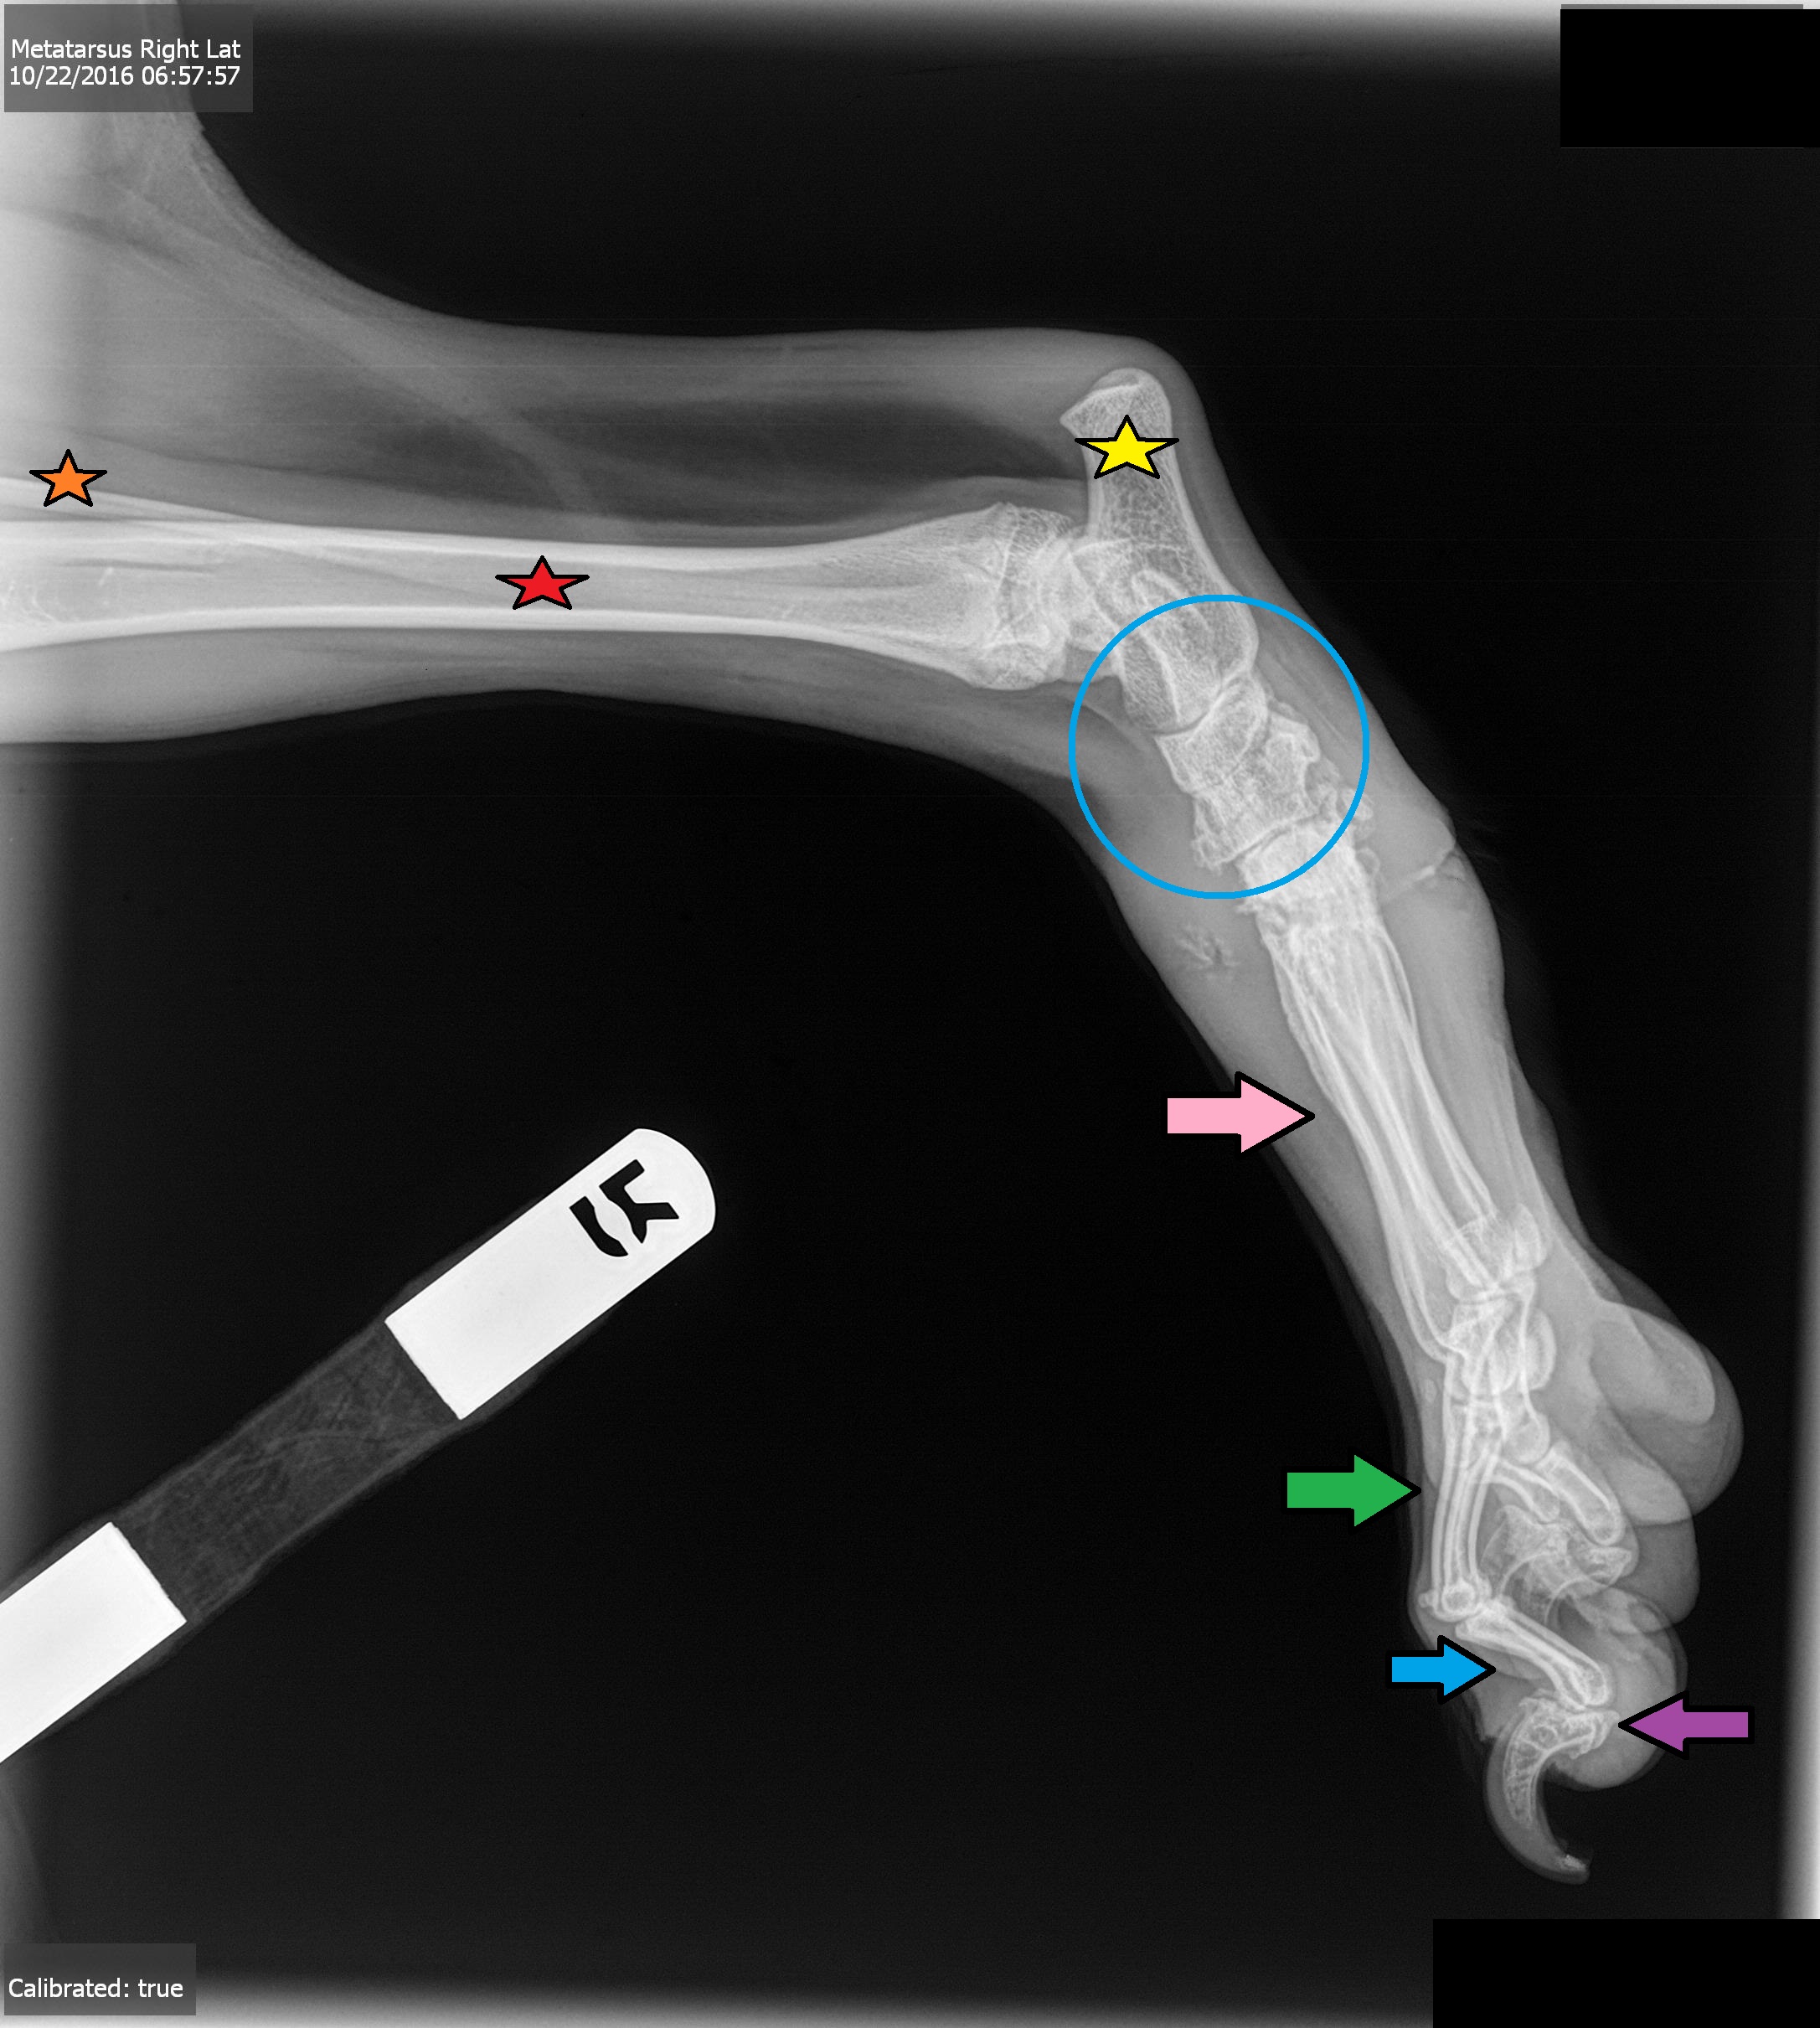

Red Arrow

Medial Sesamoid Bone

Orange Star

Fibula Bone

Red Star

Tibia Joint

Yellow Star

Calcaneal Process

Blue Circle

Tarsus Joint

Pink Arrow\

Metatarsal Bones

Green Arrow

Proximal Phalanges, P1

Blue Arrow

Middle Phalanges, P2

Purple Arrow

Distal Phalanges, P3